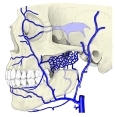

・ 静 脈 : もし血液を供給する動脈が オトガイ下動脈 であれば、静脈は オトガイ下静脈 になると思われる

が、詳細は不明。